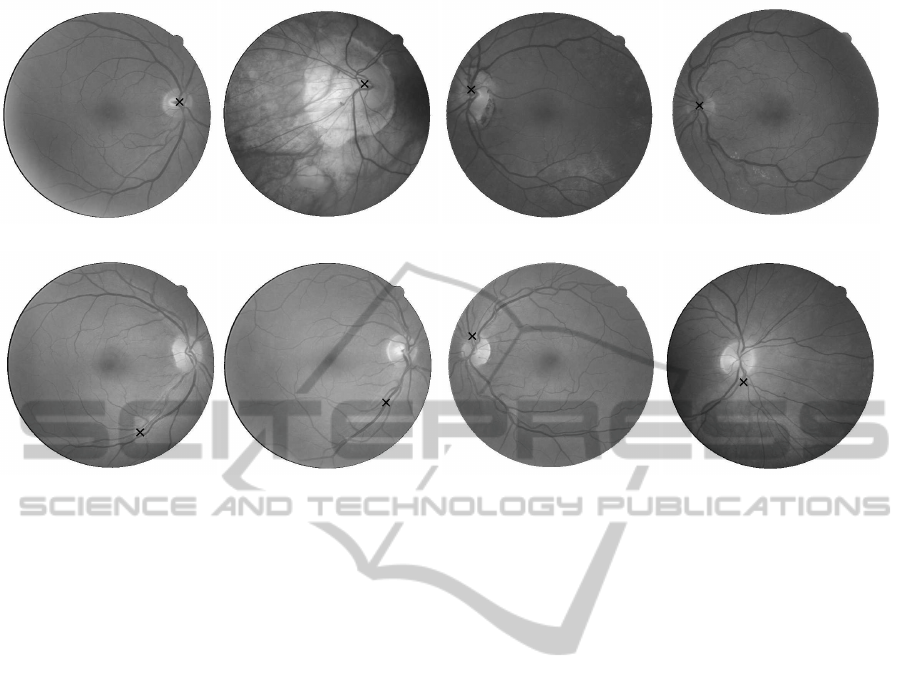

(a) (b)

Figure 1: (a) Green channel of image, (b) Result of contrast

enhancement with CLAHE.